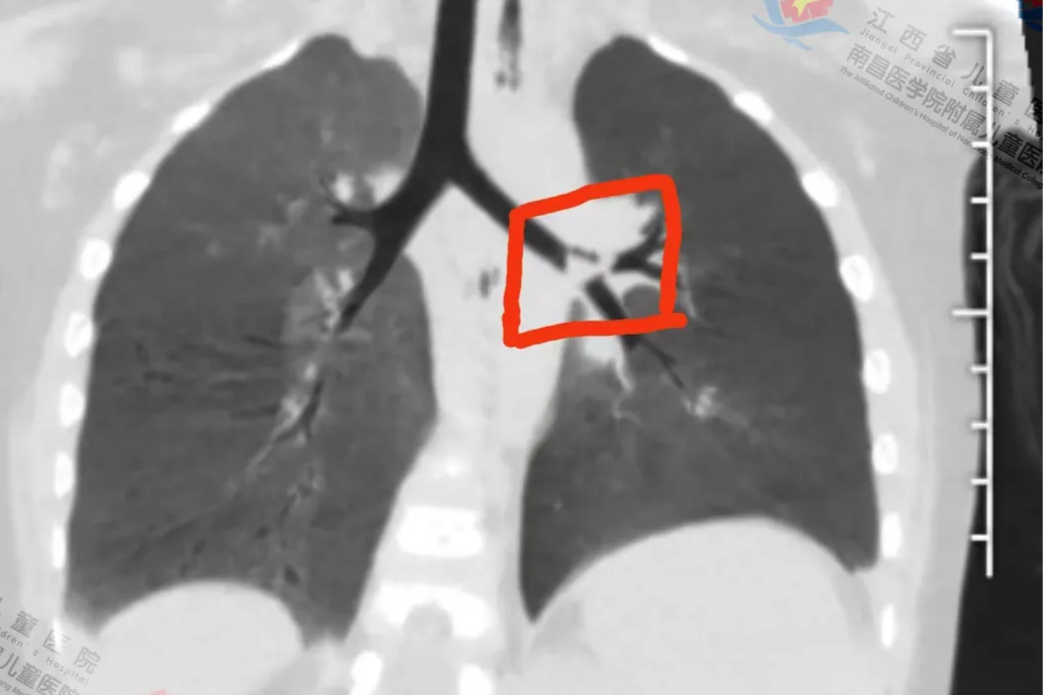

江西省儿童医院支气管镜团队助幼儿精准「擒获」支气管深部隐匿异物